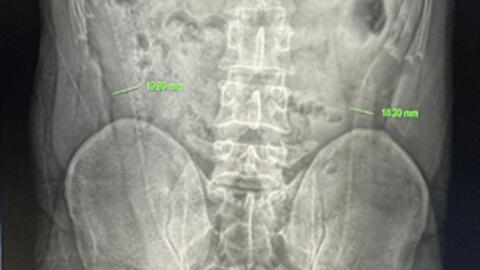

Trước đó, trưa 31/7, trong quá trình làm việc, chị N thấy buồn nôn, mệt mỏi, chóng mặt nên đã đi về nhà nghỉ ngơi. Đến khi các đồng nghiệp làm chung ngân hàng báo tin bị ngộ độc CO, chị N mới vào viện theo dõi và điều trị. Khi tiếp nhận, các bác sĩ chỉ định truyền dịch, hồi sức và dùng oxy liều cao cho sản phụ. Sau quá trình điều trị, hiện, chị N đã ổn định sức khỏe. Tiến hành siêu âm, bác sĩ xác định, em bé trong bụng mẹ vẫn ổn định, không có bất thường.